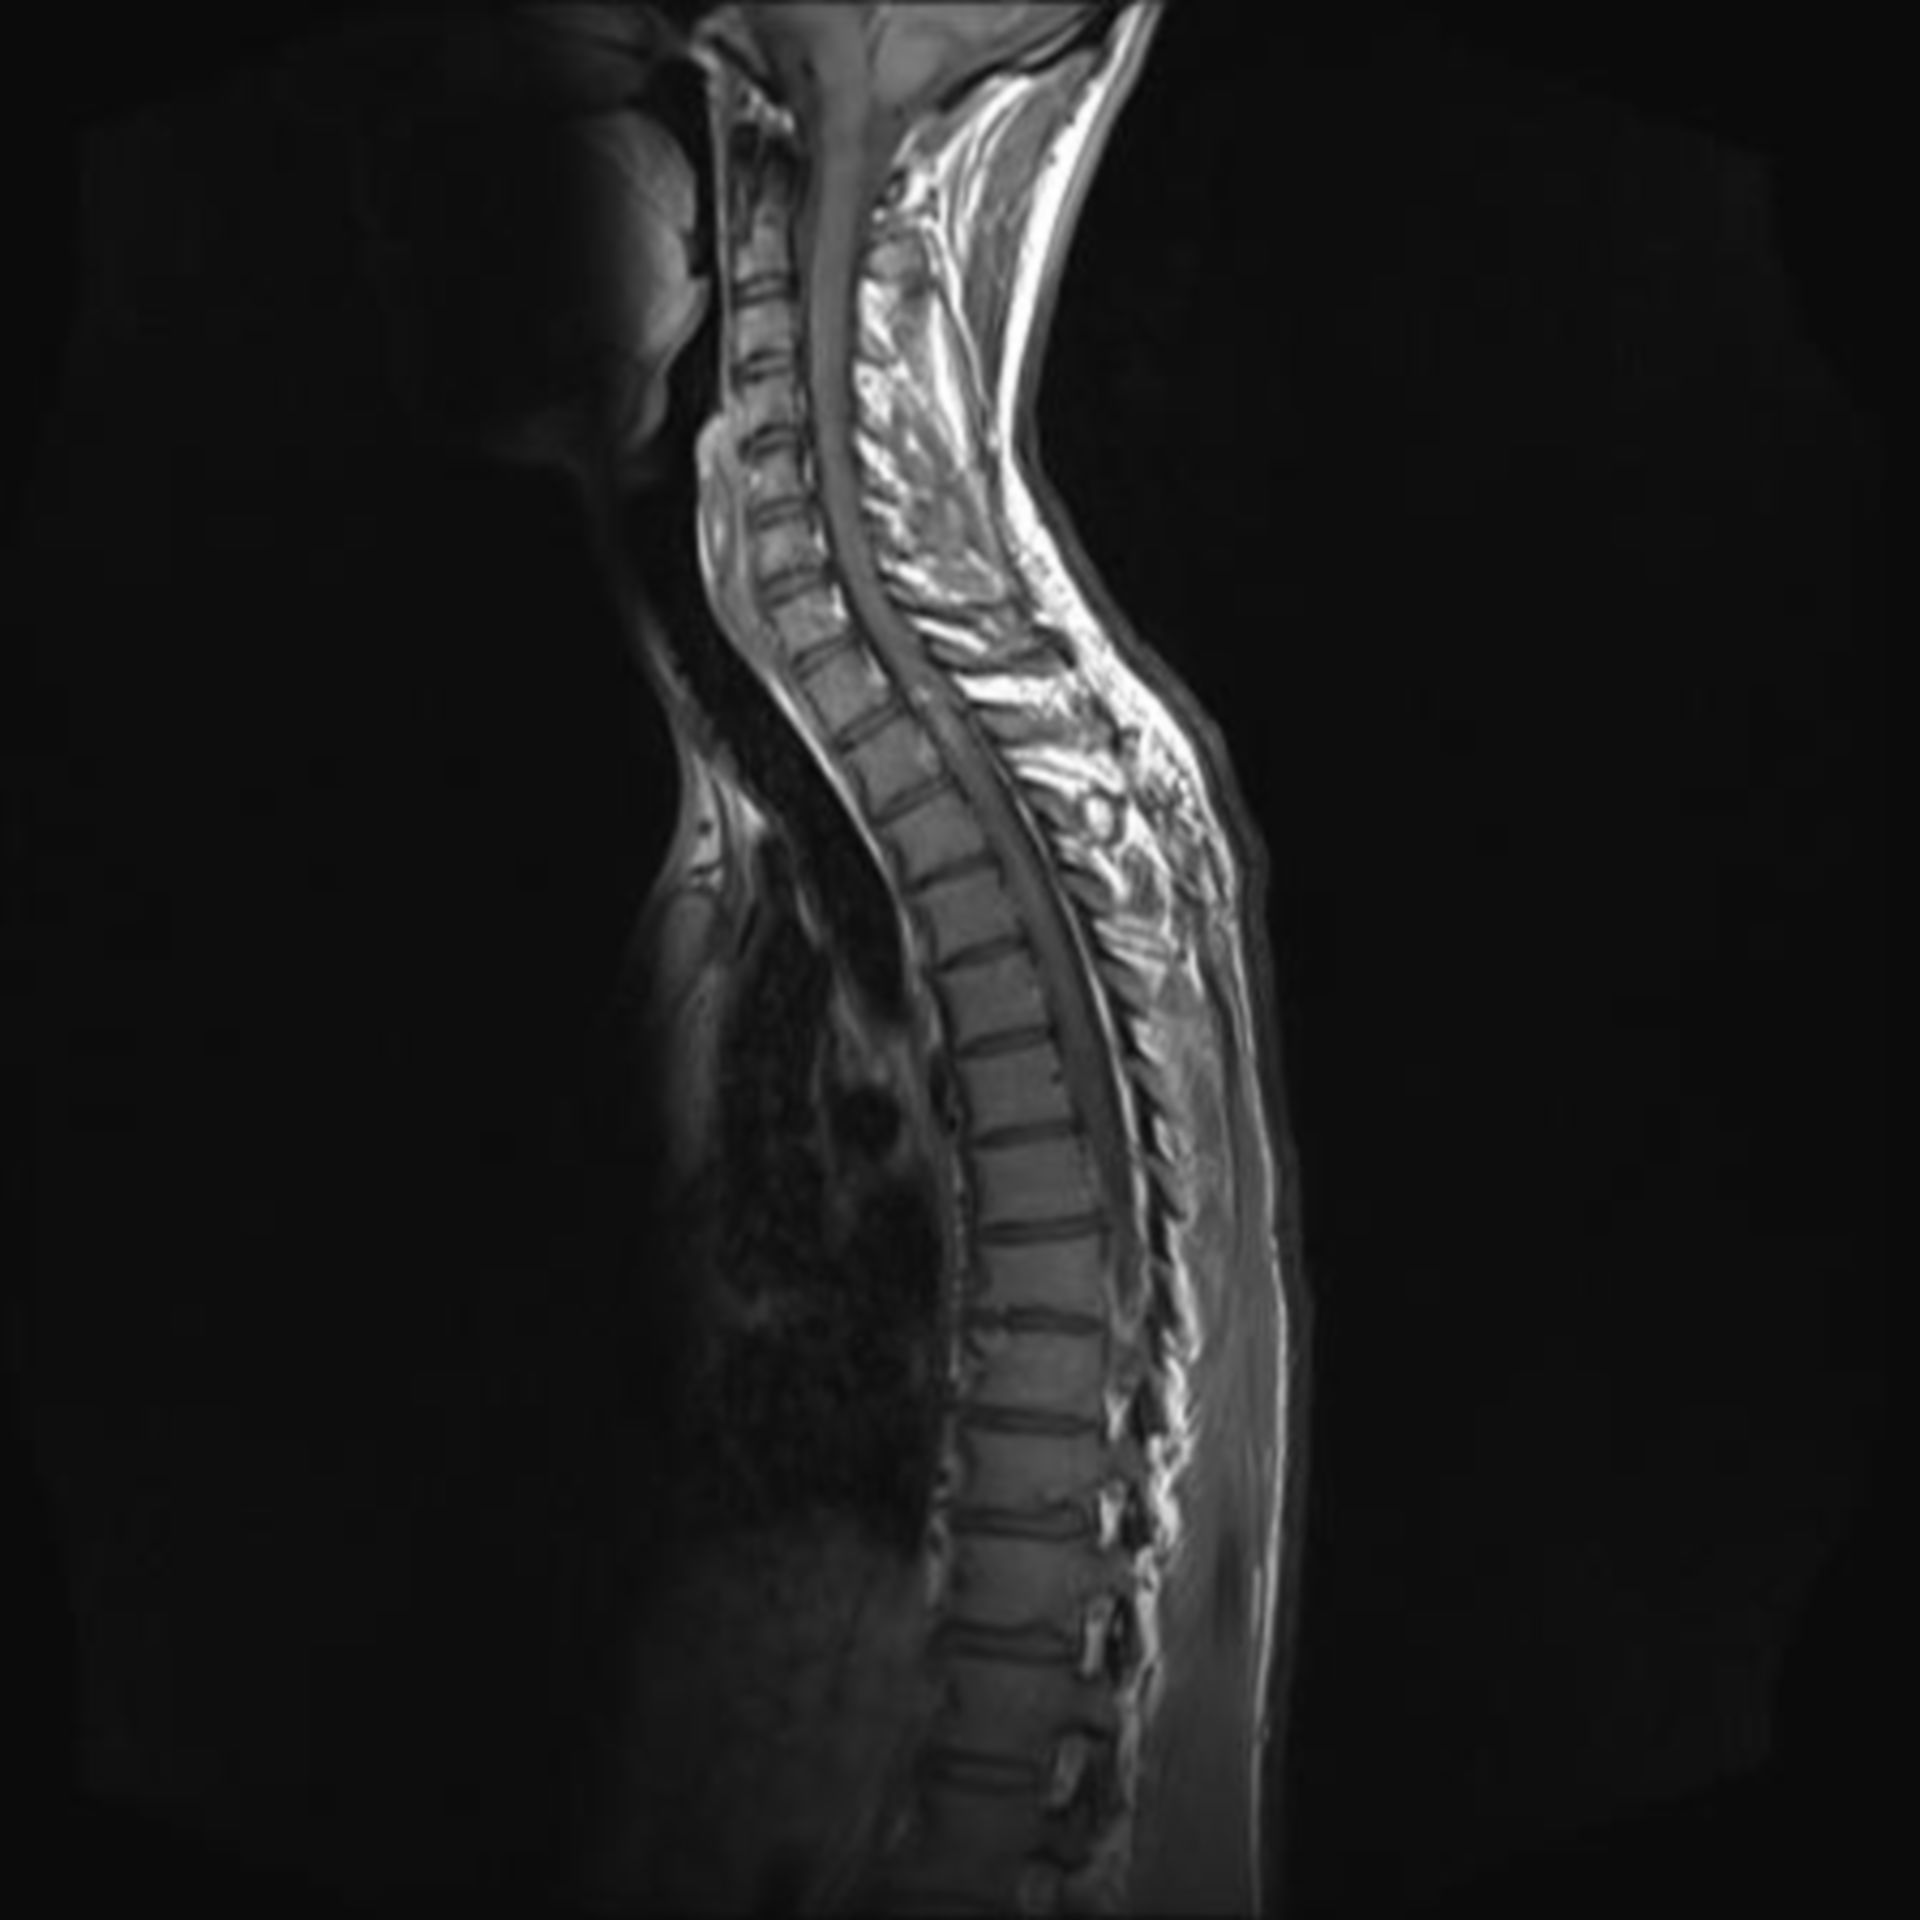

MRT HWS 1 – DocCheck

Abbildung 1: (a) MRT der HWS in T2-Gewichtung, sagittale… | Download …

Abbildung 4a-d: HWS – MRT

MRT Aufnahme der HWS Foto & Bild | industrie und technik, technik …

MRT HWS (Halswirbelsäule): Gründe, Ablauf, Dauer | praktischArzt